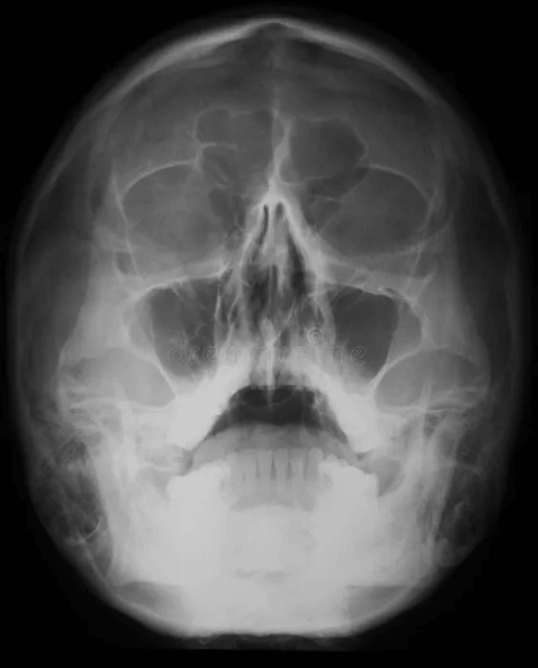

RADIOGRAFÍA POSTERO-ANTERIOR O FRONTAL

Esta radiografía sirve para evaluar el crecimiento y desarrollo facial, traumatismos, enfermedades y anomalías del desarrollo. Muestra la bóveda craneana, senos frontales y etmoidales, órbitas, cavidad nasal y la mandíbula.

Entre sus principales indicaciones se encuentran:

- Valorar asimetrías craneales

- Evaluar fracturas de bóveda craneal

- Evaluación del seno frontal

- Enfermedades que afectan el cráneo (enfermedad de Paget Ósea, mieloma múltiple, hiperparatiroidismo)

- Evaluar calcificaciones intracraneales.

Ventajas:

Entre sus principales ventajas que ofrece es la evaluación de los huesos faciales y del cráneo desde un vista postero anterior, lo cual permite evaluar diferentes aspectos en relación con el desarrollo de estos huesos, asi como secuelas traumáticas o asimetrías.